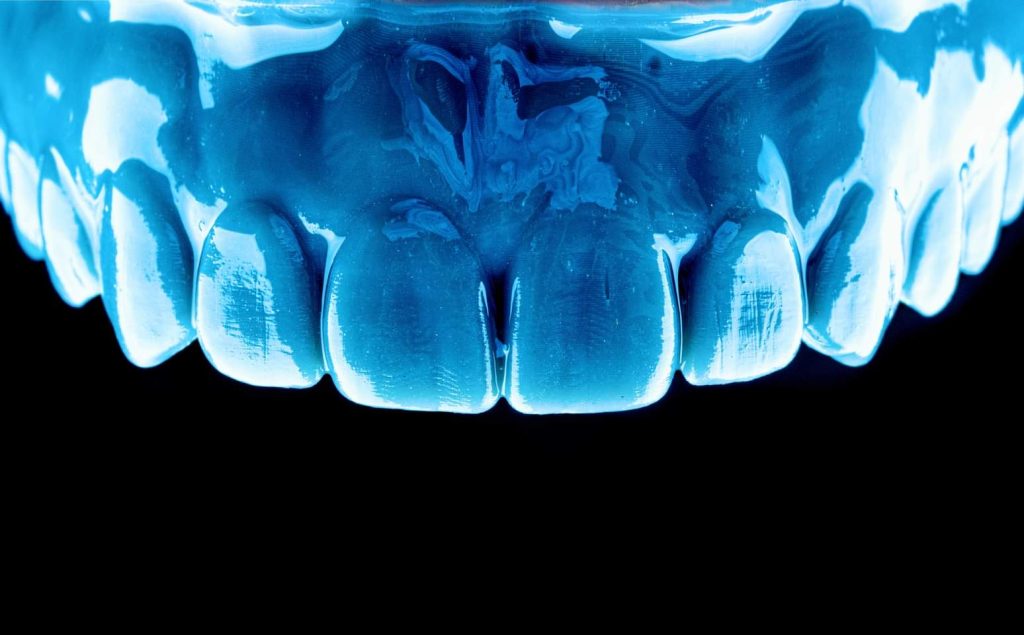

The case presented in this case report is for a 27-years-old female patient with a chief complaint of aesthetic correction for her smile. The patient was unhappy with her smile. After clinical examination, there were previous old composite veneering done poorly and incorrectly to close the multiple interdental spacing. After discussing the various treatment options (i.e., orthodontic treatment, direct, or indirect veneers), indirect ceramic veneering was selected. The step-by-step treatment protocol is presented in the images below.

Special thanks to my friend, Dr. Ali Al-Qrimli the CEO of Digital IDEA dental lab for fabrication of the ceramic veneers and the digital designing, with many thanks for the dental ceramist, Dt. Ali Kadum who did the ceramic build-up for this case.